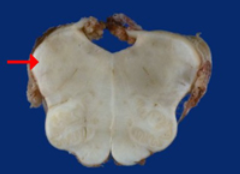

如图箭头所示为小脑哪个部位( )

A:小脑中脚

B:小脑下脚

C:小脑扁桃体

D:小脑上脚

E:小脑蚓部